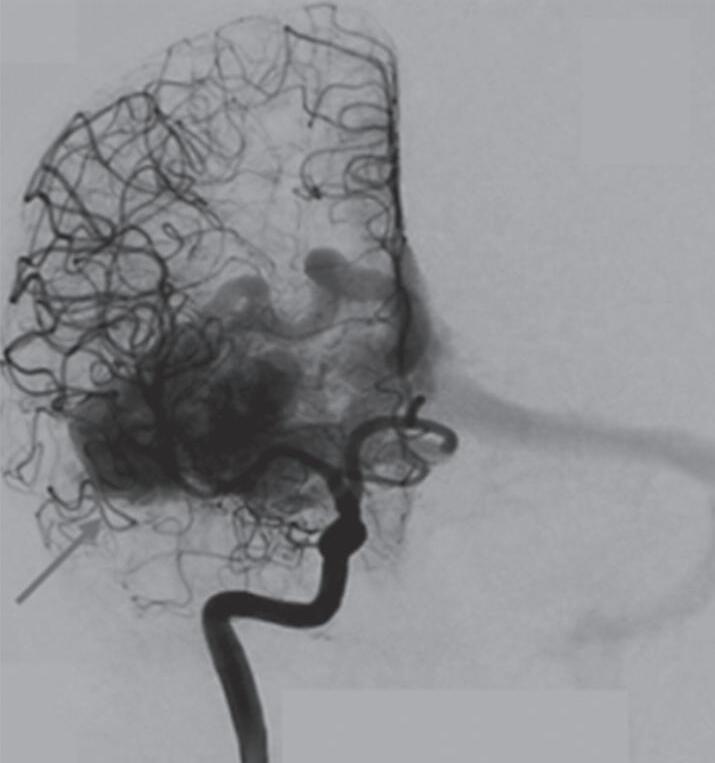

Fig. 1-8. (a-c) RNM T1 com contraste, cortes sagital (a), coronal (b) e axial (c) demonstrando MAV não rota com nidus localizado no lobo occipital à esquerda (setas longas). (d) Arteriografia digital cerebral com injeção de contraste via carótida direita (AP) mostrando a contribuição da carótida direita na irrigação da MAV contralateral. (e,f) Com injeção de contraste via carótida esquerda, em Perfil e AP respectivamente, observa-se nidus compacto nutrido por ramos da artéria cerebral média à esquerda e a veia de drenagem precoce se dirigindo para o seio sagital superior. Projeções em AP (g) e em perfil (h) demonstrando a contribuição do sistema vertebrobasilar por meio de ramos distais da artéria cerebral posterior à esquerda e drenagem para os seios sagital superior e sigmoide à esquerda (setas curtas).